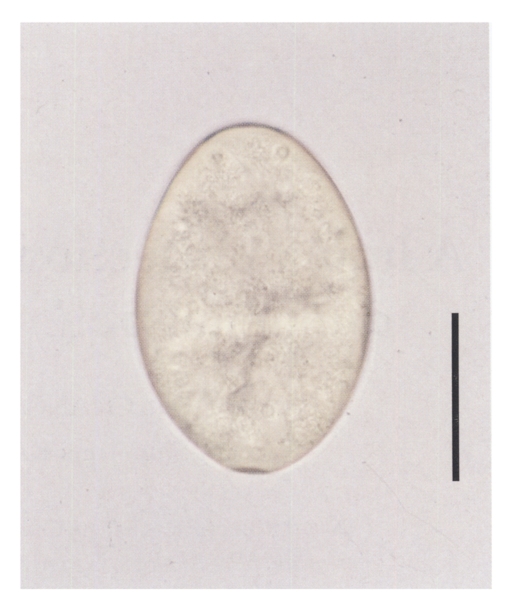

She had worked in a small restaurant, and had eaten raw frog meat several times about two months before onset of her symptoms. She denied ever eating freshwater fish in raw. Laboratory data were not available. A stool examination revealed six echinostome eggs, but none were found in family members. The eggs were bright yellow, elliptical, thin shelled with a shallow operculum, and measured 114.1 (111.2-118.6) µm long and 76.7 (74.1-79.0) µm wide (Fig. 2).